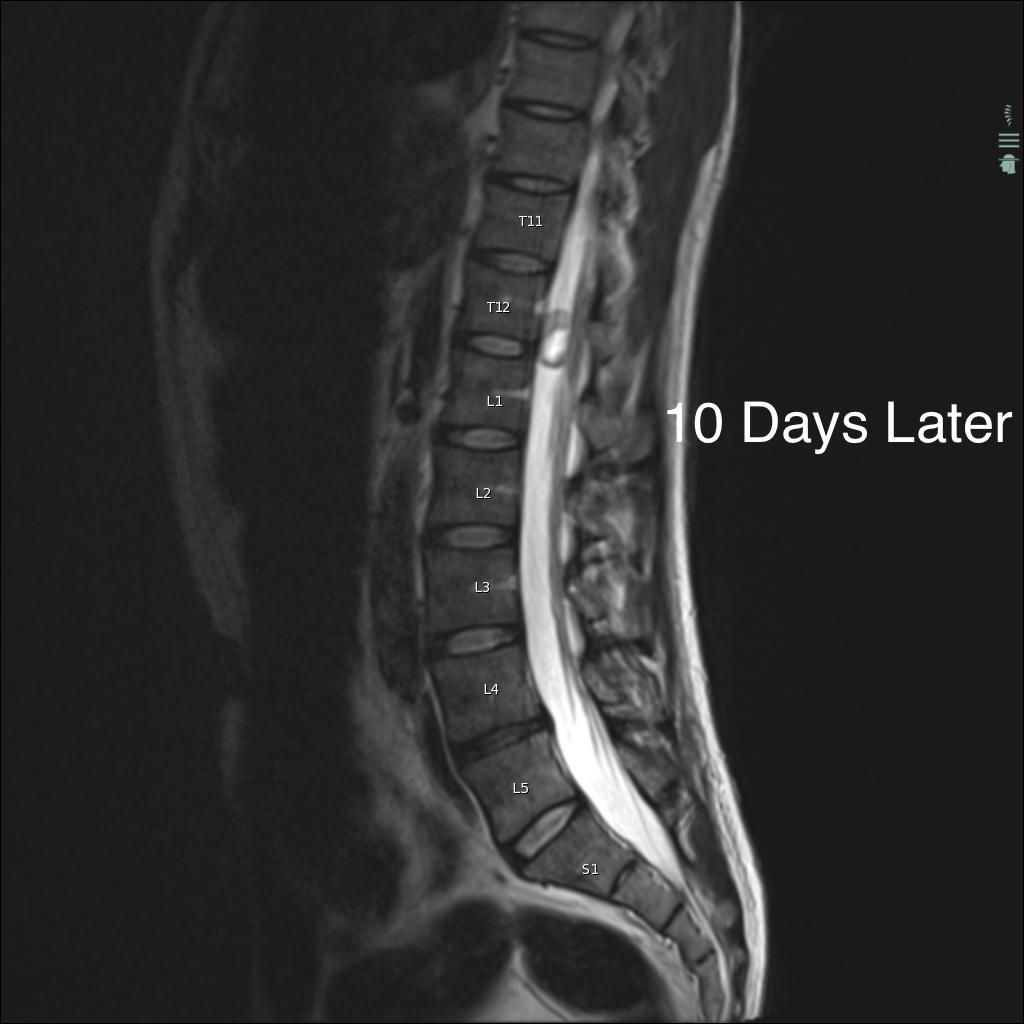

Case History: 40-year-old man with low back pain, right lower extremity paraesthesias, and incontinence. He presents 10 days later with worsening pain.

What is your diagnosis?